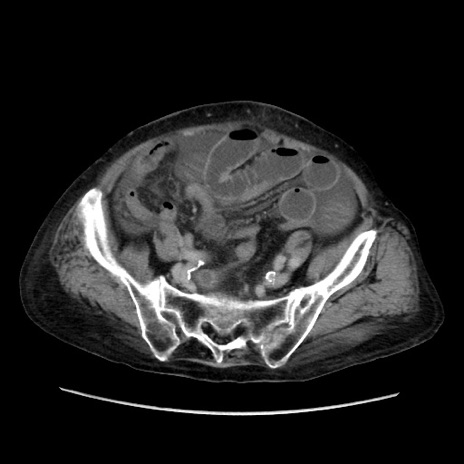

症例31(横断像)

【症例】80歳代 女性

【主訴】腹部膨満感

【現病歴】他院にて肝硬変にてフォロー中。1週間前から便秘、腹部膨満感、臍部腫瘤あり受診となる。

【既往歴】肝硬変

【身体所見】腹部膨隆あり、皮膚変化なし、疼痛なし。

【データ】WBC 4600、CRP 0.25